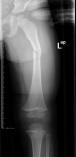

儿童陈旧性孟氏骨折

术前前臂侧位片